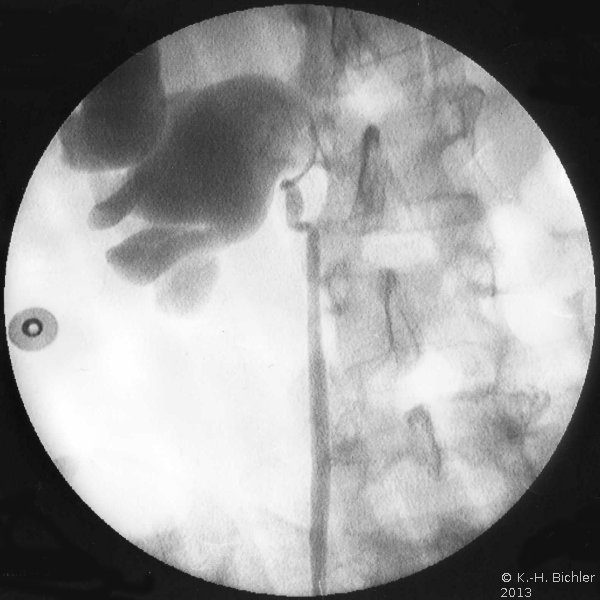

Die junge Frau kam wegen der beim Allgemeinarzt festgestellten Hypertonie (220 zu 120) und rechtsseitigem Harnstau in der Sonographie zur urologischen Abklärung. Im Isotopennephrogramm zeigte sich eine ausreichende Gesamtfunktion beider Nieren mit einer kleinen rechten Niere und entsprechend reduzierter Partialfunktion: Rechts zu links wie 72 zu 28. Beim Lagewechsel vom Liegen zum Sitzen zeigte sich keine Durchflutungsänderung bei erkennbarer rechtsseitiger Nephroptose. In der retrograden Sondierung fand sich auf der rechten Seite eine Ureterabgangsstenose, die eine Nierenbeckenplastik nach Anderson-Hynes erforderte sowie in gleicher Sitzung eine Nephropexie der rechten Niere (Abbildung 18).